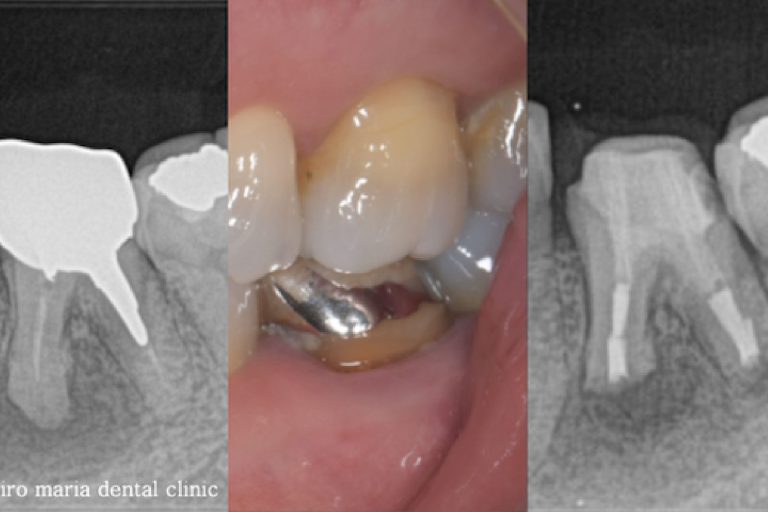

• 目白マリア歯科_意図的再植術0625メイン

【症例】意図的再植術|歯根破折歯を保存したチャレンジケース